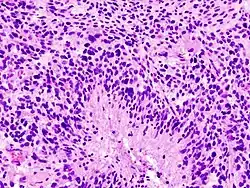

O glioblastoma surge no próprio cérebro, mais especificamente dos astrócitos, que são células responsáveis por algumas funções desta área nobre do ser humano. Quando um tumor tem sua origem definida pelos astrócitos, diz-se que é um astrocitoma. Um glioblastoma é um tipo de astrocitoma e seu grau de malignidade é o mais avançado (grau IV), ou seja, extremamente agressivo. É mais frequente em adultos entre os 35 e os 70 anos de idade, mas não é incomum ocorrer em outras idades.

O grande problema deste tipo de tumor é o seu rápido crescimento, e mesmo após a cirurgia, um novo aumento é esperado. Além disso há infiltração de células tumorais isoladas no tecido cerebral aparente normal a 7 cm de profundidade além da periferia da lesão. Mesmo que a operação remova 99,99% do tecido neoplásico, o restante infiltrado no tecido ou mínimo resíduo local é capaz de se multiplicar e dependendo do caso, volta ao tamanho inicial em até 30 dias.